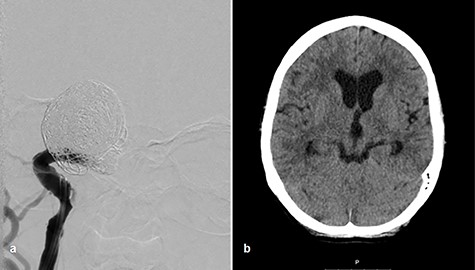

Afterward, we decided to perform aneurysm coiling and PAO. Prior to this, we repeated the occlusion test with clinical, angiographic and TCD control before and during induced arterial hypotension. In stand-by anesthesia with central venous catheter and invasive blood pressure monitoring, a 4-F catheter was placed in the left ICA and a 6-F guiding catheter was placed in the right ICA. Occlusion of the right ICA was performed with a balloon. With 100 mmHg mean blood pressure, we measured 78 m/s systolic flow in the TCD on the right MCA. The patient presented no neurological symptoms. Left ICA angiogram showed good crossflow perfusion of the right side over the anterior communicating artery. After a drop of mean blood pressure from 100 to 70 mmHg using intravenous administration of urapidil, there was no neurological deficit observed over the period of 30 min. Furthermore, there was no perfusion reduction and no delay of venous phase on the right side on the angiogram of left ICA (Fig. 2c and d), but we observed systolic flow reduction from 78 to 50 cm/s on the right MCA in the TCD during induced arterial hypotension. Based on the results of good collateral flow during occlusion test without neurological deterioration after hypotension challenge, we finally performed PAO by coiling with seven coils (Fig. 3a).

Coiling of giant aneurysm and parent vessel occlusion, p–a angiogram (a), CT scan on Day 1 (b).

After aneurysm coiling with PAO, the patient was put on dual antiaggregation therapy with aspirin 100 mg and clopidogrel 75 mg per day for the next 6 weeks, followed by aspirin alone 100 mg per day lifelong. Computed tomography (CT) scan on Day 1 presented no infarction (Fig. 3b). Perfusion CT scan on Day 9 after intervention showed regular perfusion of the right hemisphere without any cerebral blood flow/cerebral blood volume mismatch. The oculomotor palsy had subsided after 3 months.